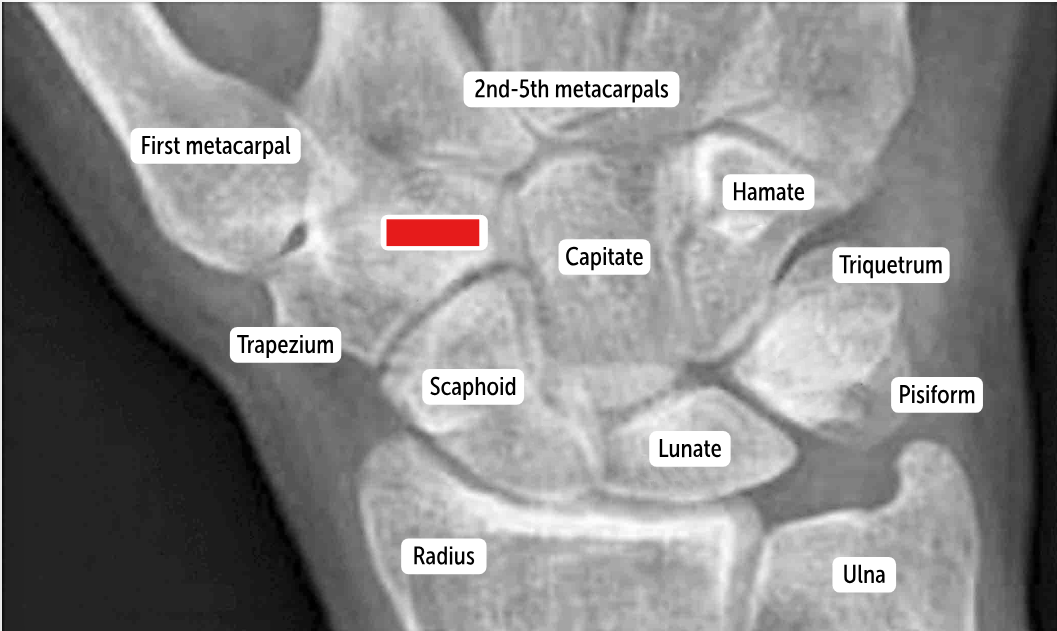

Carpal bones by row:

So Long To Pinky, Here Comes The Thumb

Scaphoid, Lunate, Triquetrum, Pisiform, Hamate, Capitate, Trapezoid, Trapezium

Scaphoid

Lunate

Triquetrum

Pisiform

Hamate

Capitate

Trapezoid

Trapezium